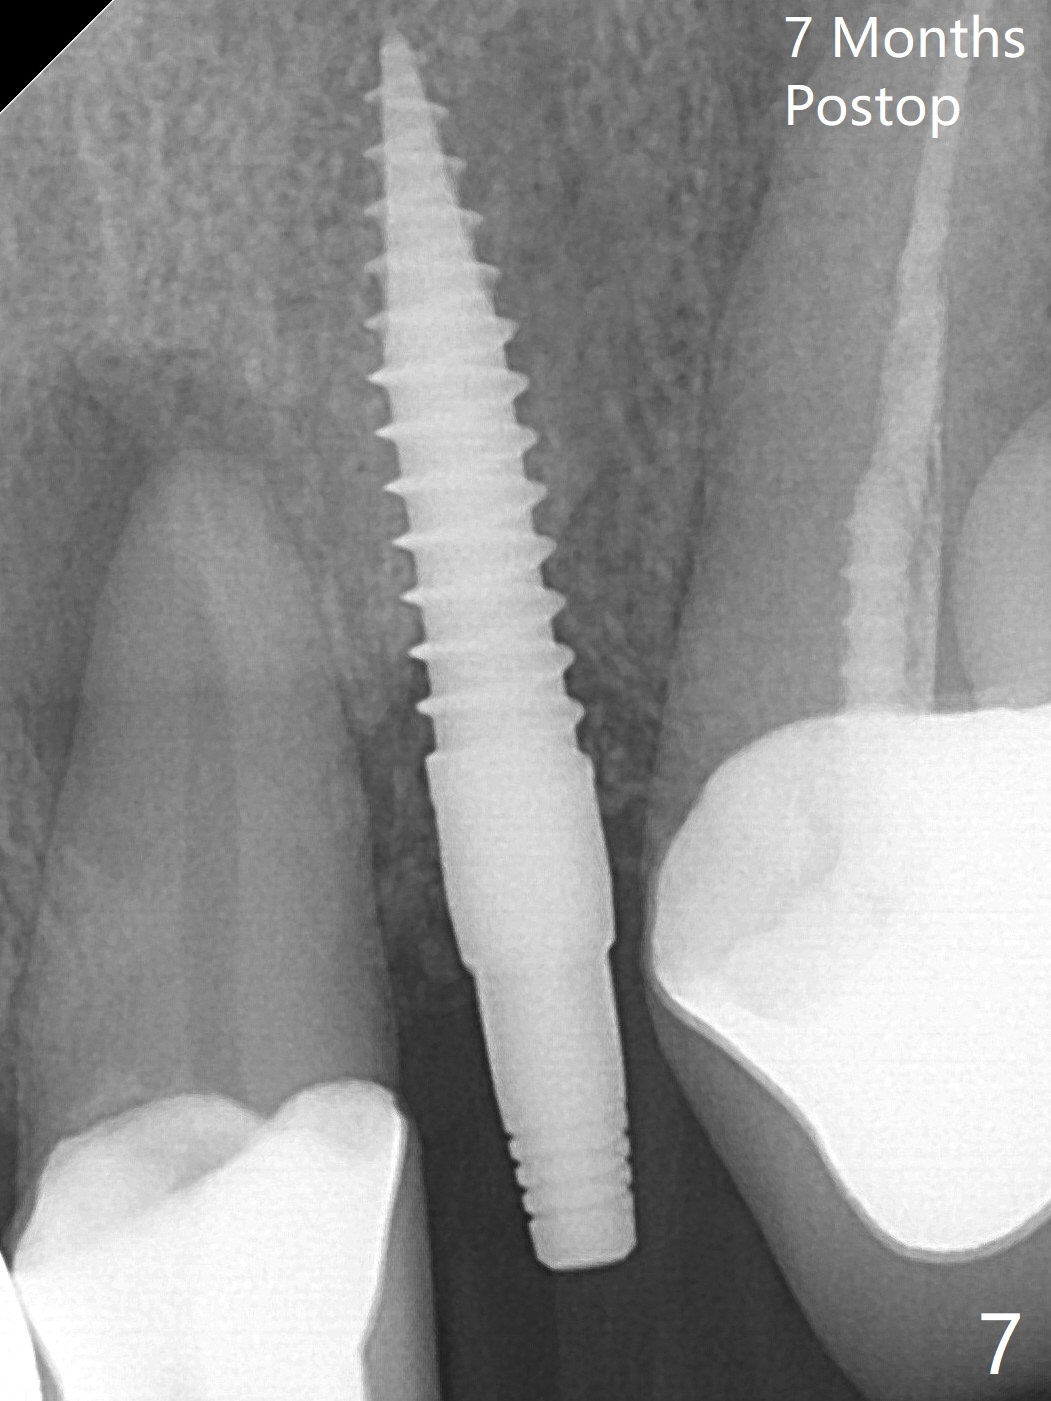

Following further distalization, a 3x14 mm implant is placed (Fig.6; <30 Ncm). Vera Graft will be placed in the remaining socket prior to provisional fabrication (*). The socket outline disappears 7 months postop (Fig.7).